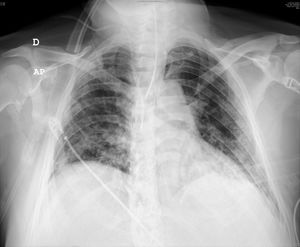

Estudio de la situación: a nivel pulmonar, en la radiografía de tórax destaca patrón alveolointersticial pulmonar bilateral respetando ambos vértices pulmonares, compatible con neumonía por COVID-19 (fig. 1). En la TAC torácica (realizada el 10.° día de ingreso en la UCI) se aprecia dudoso defecto de repleción en rama segmentaria del lóbulo inferior derecho (LID), opacidades pulmonares parcheadas en vidrio deslustrado y pequeñas consolidaciones bilaterales difusas, con engrosamiento de septos interlobulillares en lóbulo inferior izquierdo (LII), en relación con neumonía por COVID-19, informándose como posible TEP periférico en LID y hallazgos compatibles con COVID-19 (fig. 2)6.